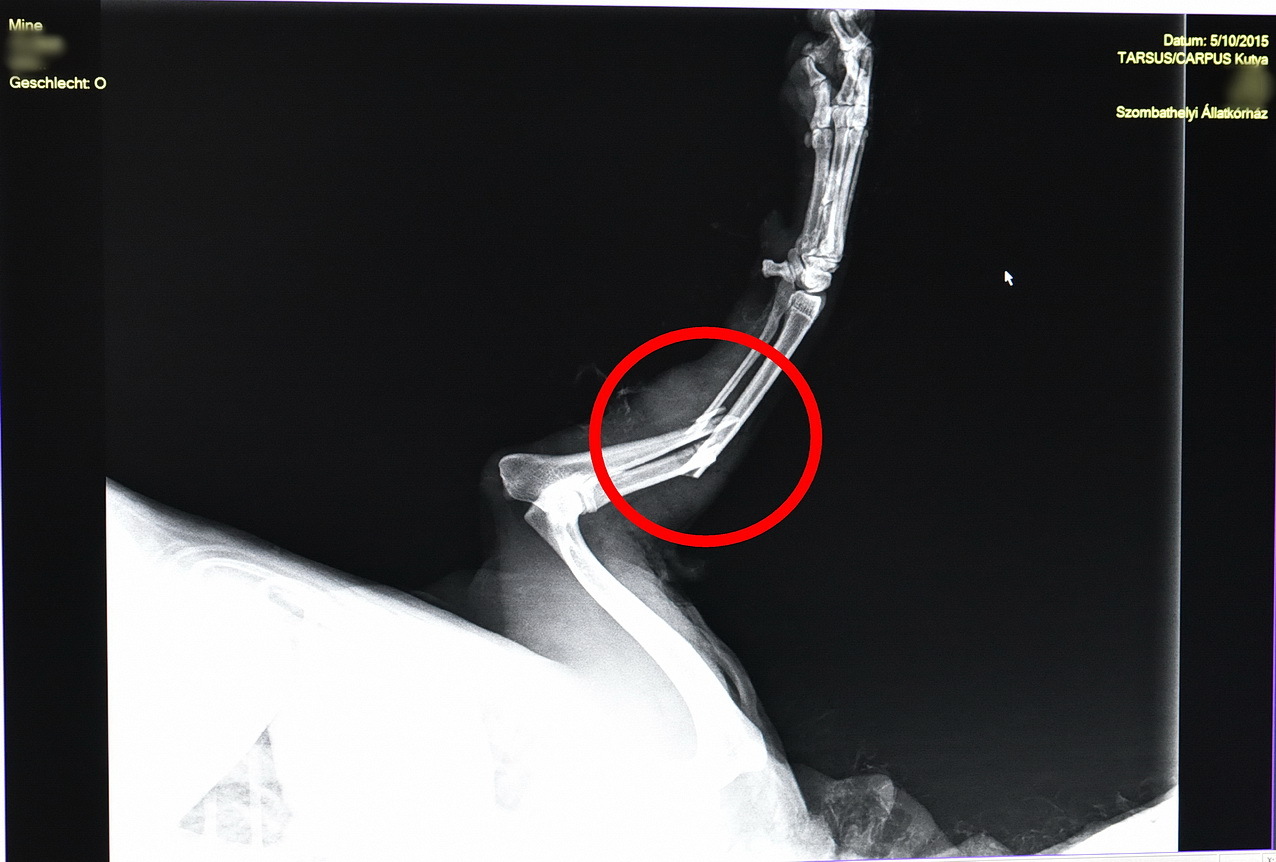

2015. május 10. Pórázon sétáltatott uszkárra támadt egy kutya Szombathelyen A támadó kutya hosszú percekig nem eresztette az uszkárt az oladi városrészben. Mine súlyosan megsérült. Kerestük a támadó kutya gazdáját is, de nem nyilatkozott. További részletekért klikk ide! címkék: kutyatámadás olad staffordshire terrier közép uszkár póráz szájkosár Hozzászólások A cikkekhez csak regisztrált felhasználóink szólhatnak hozzá.Kérjük, jelentkezzen be, vagy ha még nem tette, regisztráljon. A szerkesztőség fenntartja magának a jogot, hogy a cikkekhez nem kapcsolódó kommenteket moderálja, törölje. Vissza az előző oldalra